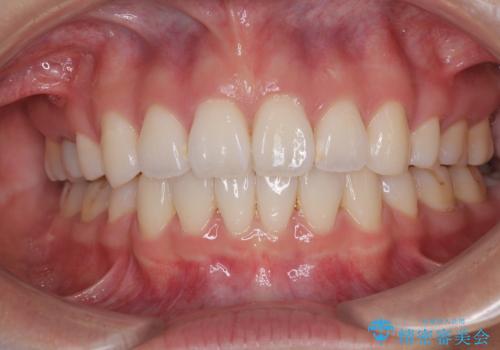

唇を閉じて眠れない ワイヤー装置での抜歯矯正で口元をスッキリと

- 前歯が突出して、眠るときに口が開いてしまうことを気にして来院された患者様です。

横から見た際の口元の飛び出した印象も改善したいとのことで、上下左右の第一小臼歯4本を抜歯し、ワイヤー装置にて抜歯矯正を行うこととしました。

舌の突出癖改善のためのトレーニングをしっかりと実践してくださり、2年強の治療期間でしっかりと仕上げることができました。